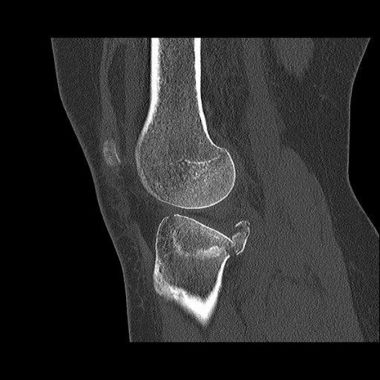

Im April 2022 versorgter außenseitiger Schienenbeinkopfbruch (Tibiakopffraktur) bei einer 35-jährigen Patientin. Bei der Versorgung wurde anhand der CT – Untersuchung die außenseitige kniekehlenwärts gelegene Gelenkflächenabsenkung wieder angehoben und mit Knochen unterfüttert. Intraoperativ wurde mit Hilfe der Arthroskopie die Gelenkfläche überprüft. Anschließend wurde die Rekonstruktion durch die seitliche und hintere Platte sowie zusätzliche Schrauben stabilisiert. Nach der Operation konnte das Knie steigernd bewegt und zunächst mit einer Teilbelastung an Unterarmgehstützen belastet werden. Nach 3 Monaten ist die freie Belastung bei guter Beweglichkeit wieder erzielt worden.